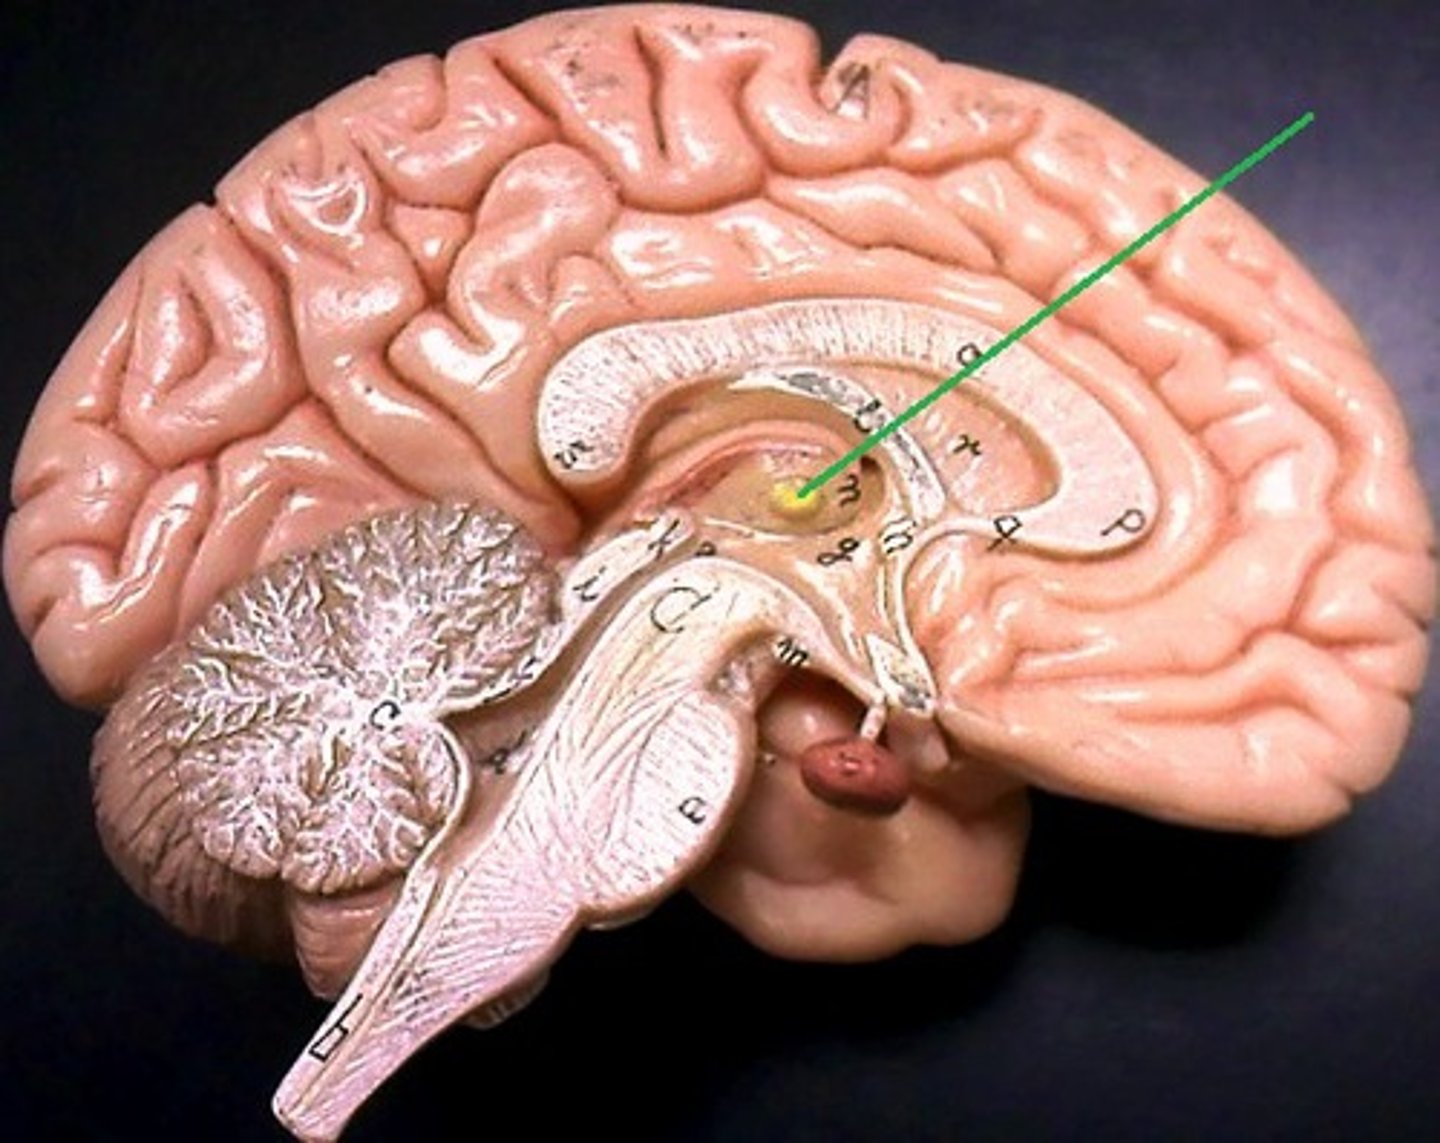

lateral ventricles

third ventricle

fourth ventricle

interventricular foramen

connects lateral ventricles to third ventricle

cerebral aqueduct

connects the third and fourth ventricles

choroid plexus

on the floor of all the ventricles, produces CSF

arachnoid villi

diencephalon

thalamus and hypothalamus

thalamus

relay station for all somatosensory information

intermediate mass

connection between the two thalami across the third ventricle, dumbbell shape

hypothalamus

brain region (many nuclei) in charge of maintaining homeostasis

pituitary gland

produces hormones

mammillary bodies

olfactory relay stations

epithalamus

region above midbrain that contains pineal gland

pineal gland

regulates sleep-wake cycles, secretes melatonin

cerebellum

balance, equilibrium, gross motor movement

corpus callosum

the large band of neural fibers connecting the two brain hemispheres and carrying messages between them

septum pellucidum

membrane that separates lateral ventricles

basal nuclei

internal masses of gray matter, smooth out motor movement

fornix

band under septum pellucidum